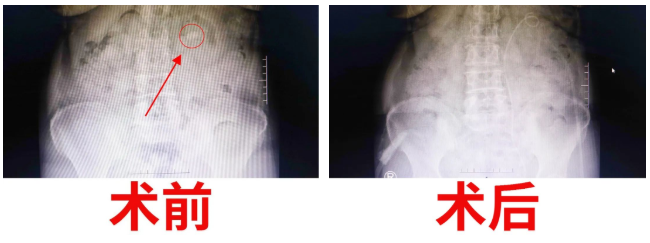

經(jīng)過泌尿外科醫(yī)護(hù)人員的密切觀察和精心護(hù)理,手術(shù)后的第三天,復(fù)查X光片,發(fā)現(xiàn)腎結(jié)石已消失得無影無蹤?!坝辛诉@樣先進(jìn)的機(jī)器,以及泌尿外科醫(yī)生團(tuán)隊(duì)高超的技術(shù),我們腎結(jié)石患者再也不用受病痛之苦了,這真是我們廣大腎結(jié)石患者的福音啊?!被颊呒拥倪B聲道謝。一周后康復(fù)出院。